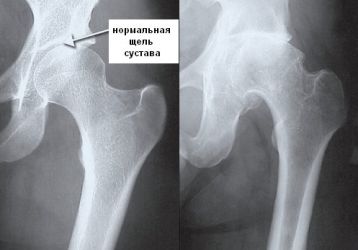

Что такое коксартроз тазобедренного сустава и как его лечить, симптомы, полное описание заболевания

Причины развития коксартроза тазобедренного сустава, характерные симптомы. 4 степени развития патологии, методы диагностики. Все способы лечения недуга. Профилактика заболевания.